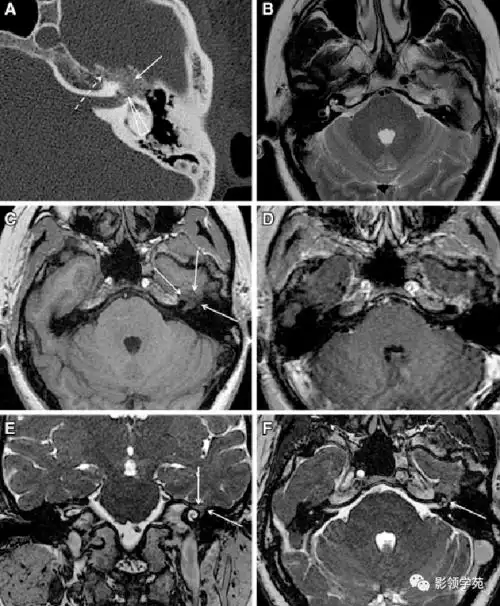

三叉神经痛,面肌痉挛手术前的主要影像学检查

面神经解剖及常见病变影像诊断

面神经解剖及相关病变